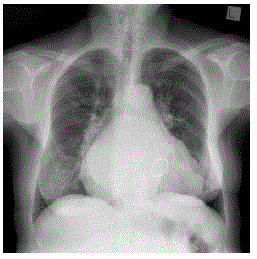

Disciplina: Medicina

Banca: UPENET/IAUPE

Orgão: SES-PE

Residência em Medicina - Cardiologia